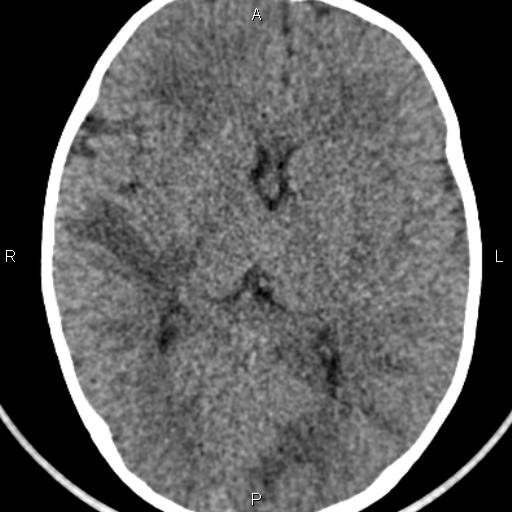

Информация о диссеминированном рассеянном энцефаломиелите